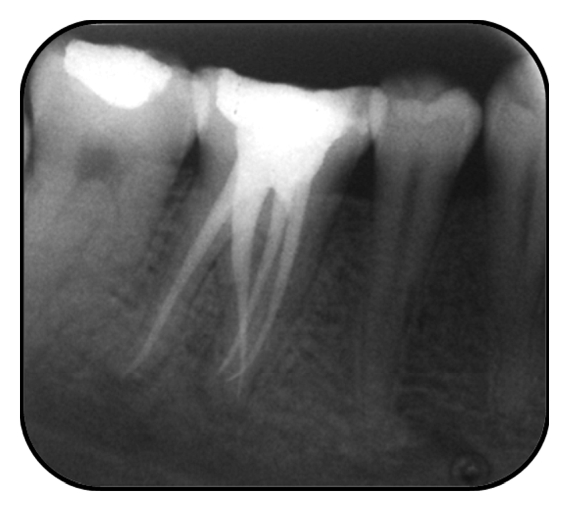

Case 1. A 22-year-old Indian female patient reported complaining of pain in a lower-right posterior tooth for a few days. The lower right first molar tooth had been restored with an amalgam restoration 10 years prior to this. Examination of the tooth revealed a large occlusal amalgam restoration with marginal ditching and tenderness to percussion. The mobility of the tooth was within physiologic limits and vitality testing revealed the tooth to be nonvital. The medical history of the patient was noncontributory. Radiographic examination (Figure 1(a)) revealed the restoration close to the distal pulp horn and periapical lamina dura widening. It also revealed the presence of an additional supernumerary root on distolingual side. In addition, a computed tomographic scan (Figures 1(b), 1(c), and 1(d)) of the lower jaw of the patient was available for surgical reasons. On evaluation, the scan illustrated the nature of origin and curvature of the extra root in a mesiobuccal direction as depicted by the arc (Figure 1(d)). The extra root originated from the distolingual part of the tooth and curved mesially.

A diagnosis was made as chronic apical periodontitis due to pulpal necrosis of the lower right first molar tooth. The pulp chamber was accessed and two mesial canal orifices and one distal canal orifice were located. In addition a dark line guided the operator towards an extra orifice located towards the distolingual part of the pulpal floor (Figure 1(e)). The root canal orifices were enlarged using gates glidden drills (Mani Inc., Kiyohara industrial park, Utsunomiya, Japan) to obtain a straight line access which modified the access shape to a more trapezoidal form. The root canals were explored with precurved K-file ISO number 15 (Dentsply Maillefer, Ballaigues, Switzerland), and radiographic length measurement was performed (Figure 1(f)). The root canals were instrumented using the ProTaper rotary files (Dentsply Maillefer, Ballaigues, Switzerland) in all the canals. During instrumentation adequate irrigation was performed using 1% sodium hypochlorite (I-Dent, Rohini, Delhi, India) and lubricated using Glyde (Dentsply Maillefer, Ballaigues, Switzerland). Obturation of the root canals was performed using AH plus sealer (Dentsply, Maillefer, Ballaigues, Switzerland) and corresponding ProTaper gutta percha points (Figure 1(g)). Postendodontic coronal restoration was done with full metal crown (Figure 1(h)).